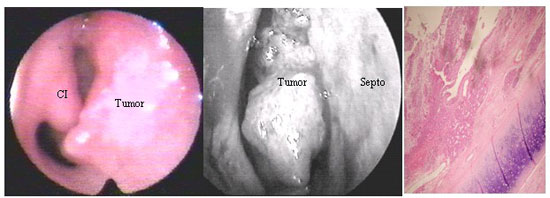

Ao exame otorrinolaringológico: fossa nasal direita apresentava massa tumoral com aspecto verrucoso, róseo, macio e sangrante à manipulação, não pulsátil, implantado em septo nasal, ocluindo a via aérea.

Nasofibroscopia revelou lesão vegetante originada na região anterior do septo nasal, estando preservados assoalho e parede lateral. Tomografia Computadorizada (TC) dos seios da face mostrou acometimento do septo nasal à direita em áreas III e IV de Cottlè e cisto de retenção em seio maxilar esquerdo. TC cervical revelou linfonodomegalia reacional. A biópsia tumoral revelou Carcinoma Mucoepidermóide. O tumor foi classificado com T1, N0, M0.

Carcinoma Mucoepidermóide de Septo Nasal

Visões endoscópicas e microscópica (HE, 100x) do mucoepidermóide septal. CI: Corneto Inferior Direito.